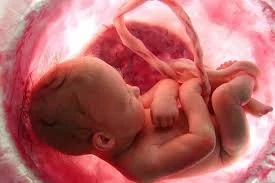

El embrión pasa a llamarse feto. Mide aproximadamente 2.3 cm y pesa alrededor de 2 gramos. Los órganos principales están formados, aunque no completamente desarrollados. La cabeza representa la mitad del tamaño del cuerpo. Los genitales empiezan a desarrollarse, aunque aún no son visibles. Los movimientos del feto son espontáneos, aunque imperceptibles para la madre.

• Semana 10

Semana 10

El feto mide alrededor de 3.1 cm y pesa unos 4 gramos. Los brazos y piernas se alargan y los dedos de las manos y los pies están completamente formados, aunque aún palmeados. Los órganos internos continúan desarrollándose, y el cerebro empieza a formar conexiones importantes. El feto ya puede mover los brazos y las piernas.